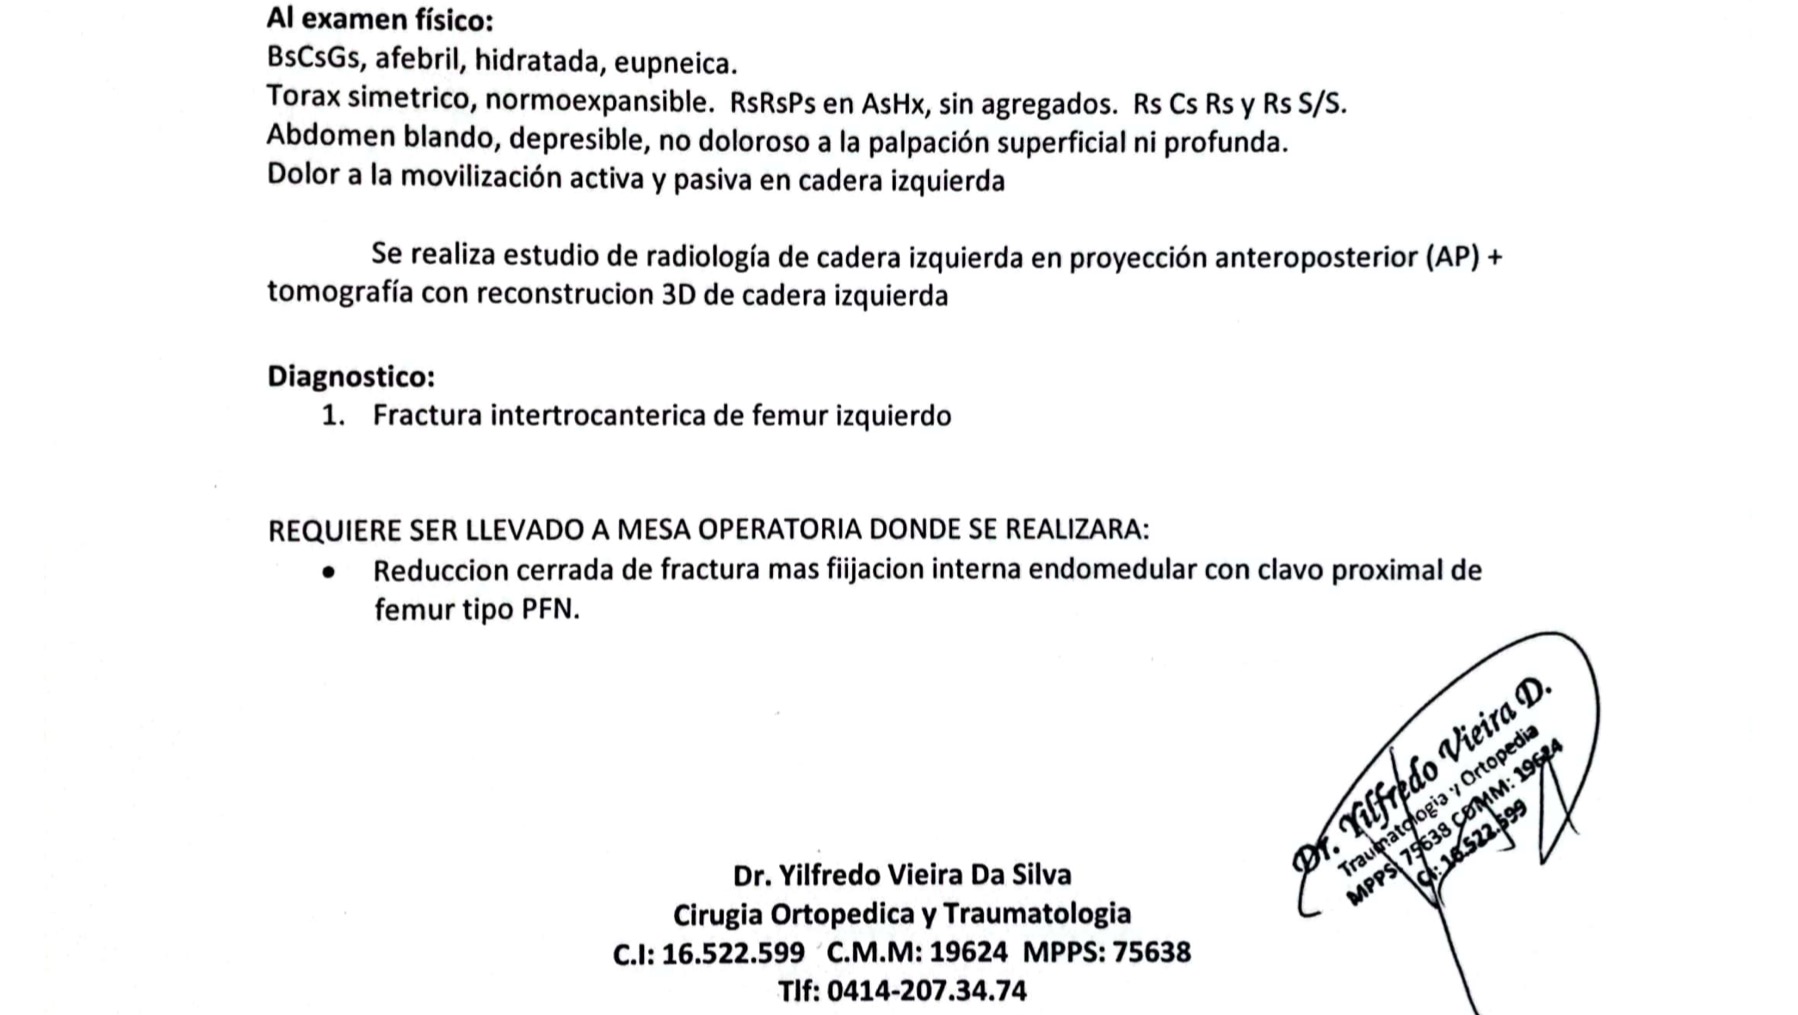

I’m reaching out today to share a difficult situation my brother is going through. He was recently hit by a motorcycle and suffered a severe hip fracture. On top of this, he has been battling diabetes for over 10 years, which complicates his condition even further.

My brother has always been a hardworking, entrepreneurial person, and he runs a family restaurant that he has kept afloat with tremendous effort. However, the economic situation in Venezuela makes it impossible for him to cover the cost of the surgery he desperately needs. The surgery itself costs around $8,000, and when you add the additional medical expenses, therapy, and the ongoing care he'll need during his recovery, the total surpasses $11,000.

He is the father of three children, and due to his injury, he will be bedridden for several months. Sadly, at the public hospital in our city, Los Teques, we were told that the waiting time for this type of surgery could be 6 to 12 months—time that his health simply cannot afford.